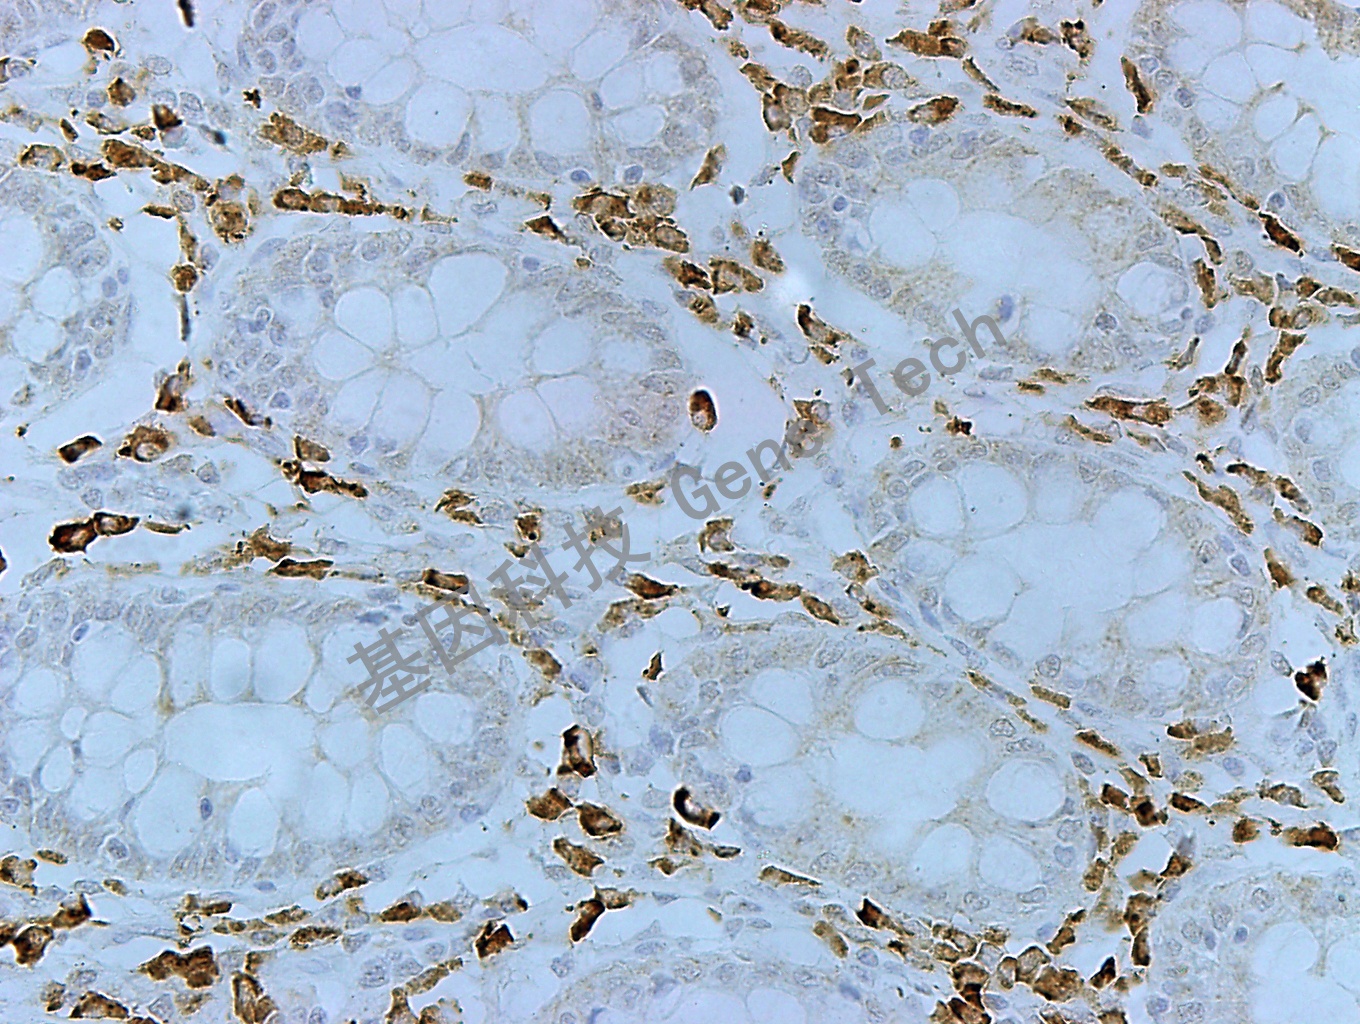

结肠癌石蜡切片,用 MUC-6(GT2220)染色,细胞浆阳性,DAB 显色。